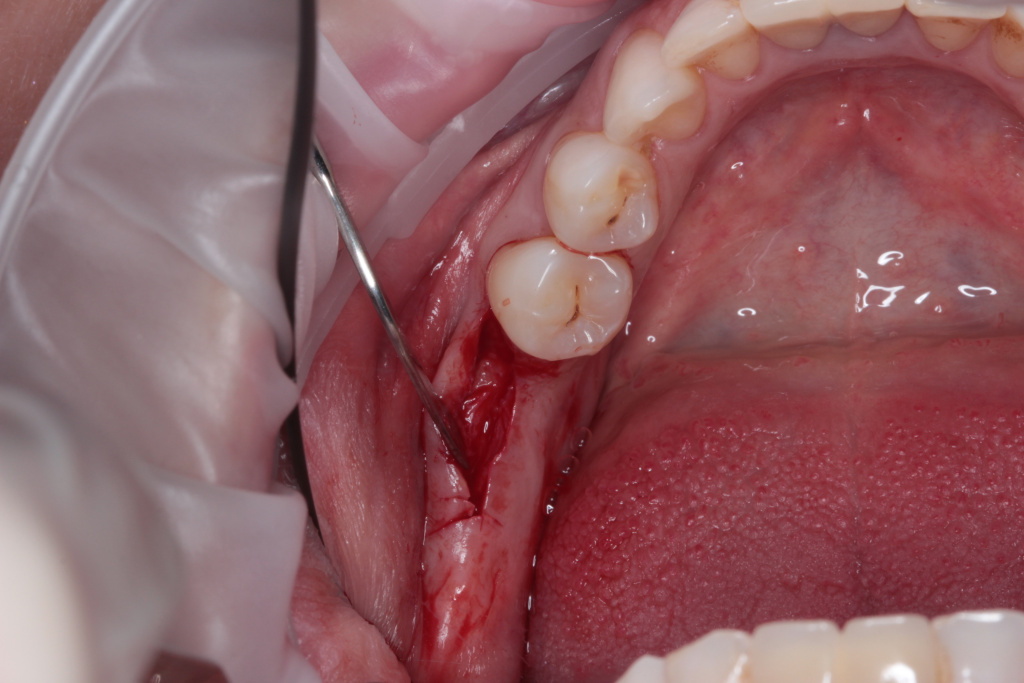

- Атравматичное удаление

- Пластика десны

- Использование костной ловушки BonePen для сбора костной стружки

- Использование фибринового сгустка APRF